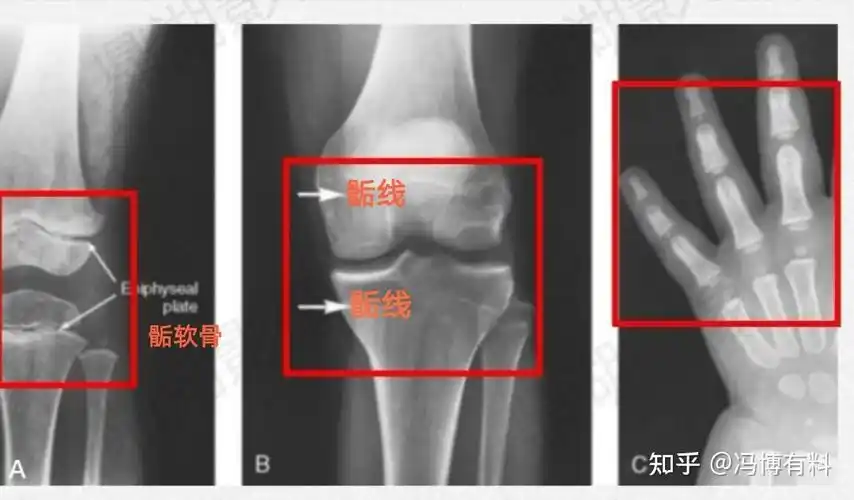

个子矮什么原因? - 知乎